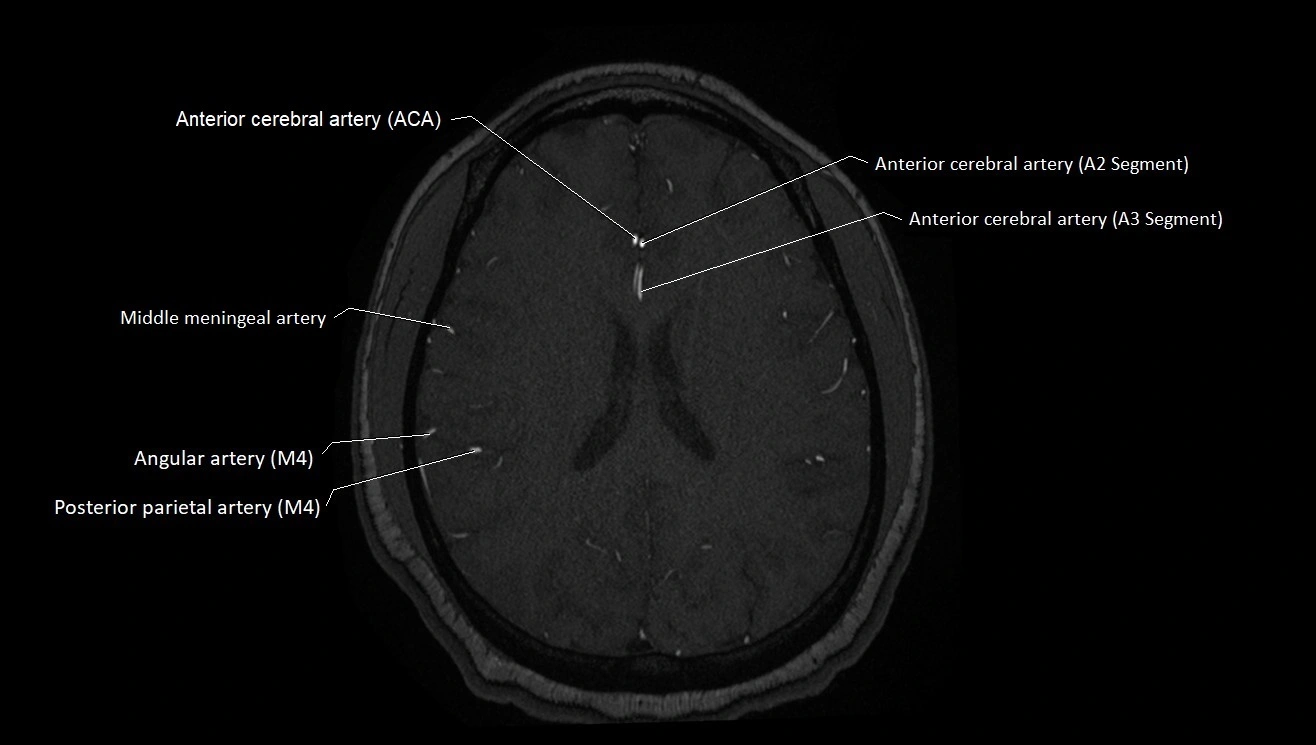

T1-weighted images:

• Vessel appears as a flow void (dark lumen) near the optic tract and temporal horn

• Surrounding parenchyma intermediate signal

T2-weighted images:

• Vessel lumen shows dark flow void

• Ischemic infarcts in its territory (internal capsule, thalamus) appear hyperintense

FLAIR:

• Vessel not seen directly; infarcts in AChA territory appear as hyperintense cortical/subcortical changes

• Chronic infarcts show gliotic hyperintensity

T1 Post-Gadolinium:

• Normal AChA enhances brightly and uniformly

• Abnormal focal enhancement indicates aneurysm, vasculitis, or AVM involvement